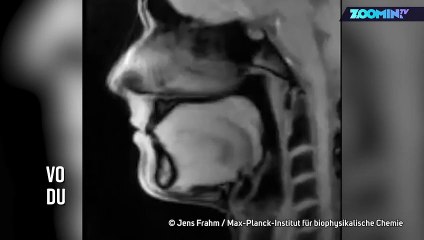

Nouvelles méthodes de diagnostic du corps humain : une approche non invasive br De tout temps, l’homme a cherché à approfondir sa connaissance du corps humain. br L’apparition de techniques de plus en plus sophistiquées, la révolution des calculateurs, la mise au point d’appareils de plus en plus sensibles ont totalement révolutionné les méthodes diagnostiques ,largement aidées par des avancées remarquables en électronique et en physique . Un fait absolument marquant est la croissance vertigineuse des application de l’IRM, entre autre, qui permet actuellement de « voir un cerveau qui pense avec des résultats strictement impensables il y a seulement cinq ans ! br Christian Brevard, membre de l'Académie des technologies, fait un tour d’horizon de quelques applications diagnostiques présentées lors de la séance du 12 juin 2013.